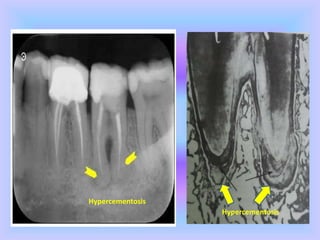

1. Hypercementosis

 It is an age-related phenomenon and refers to

prominent thickening of cementum.

 It may be localized to one tooth or affects entire

dentition.

 Occurs as generalized thickening of cementum

with nodular enlargement of apical third of root.

 It appears as spike like excrescences, created

either by coalescence of cementicles or

calcification of PDL fibres at site of insertion into

cementum.

 Roots appear thick with rounded apices.

 The causes can of hypercementosis can be:

accelerated elongation of tooth, inflammation,

tooth repair or Paget’s disease.

Hypercementosis